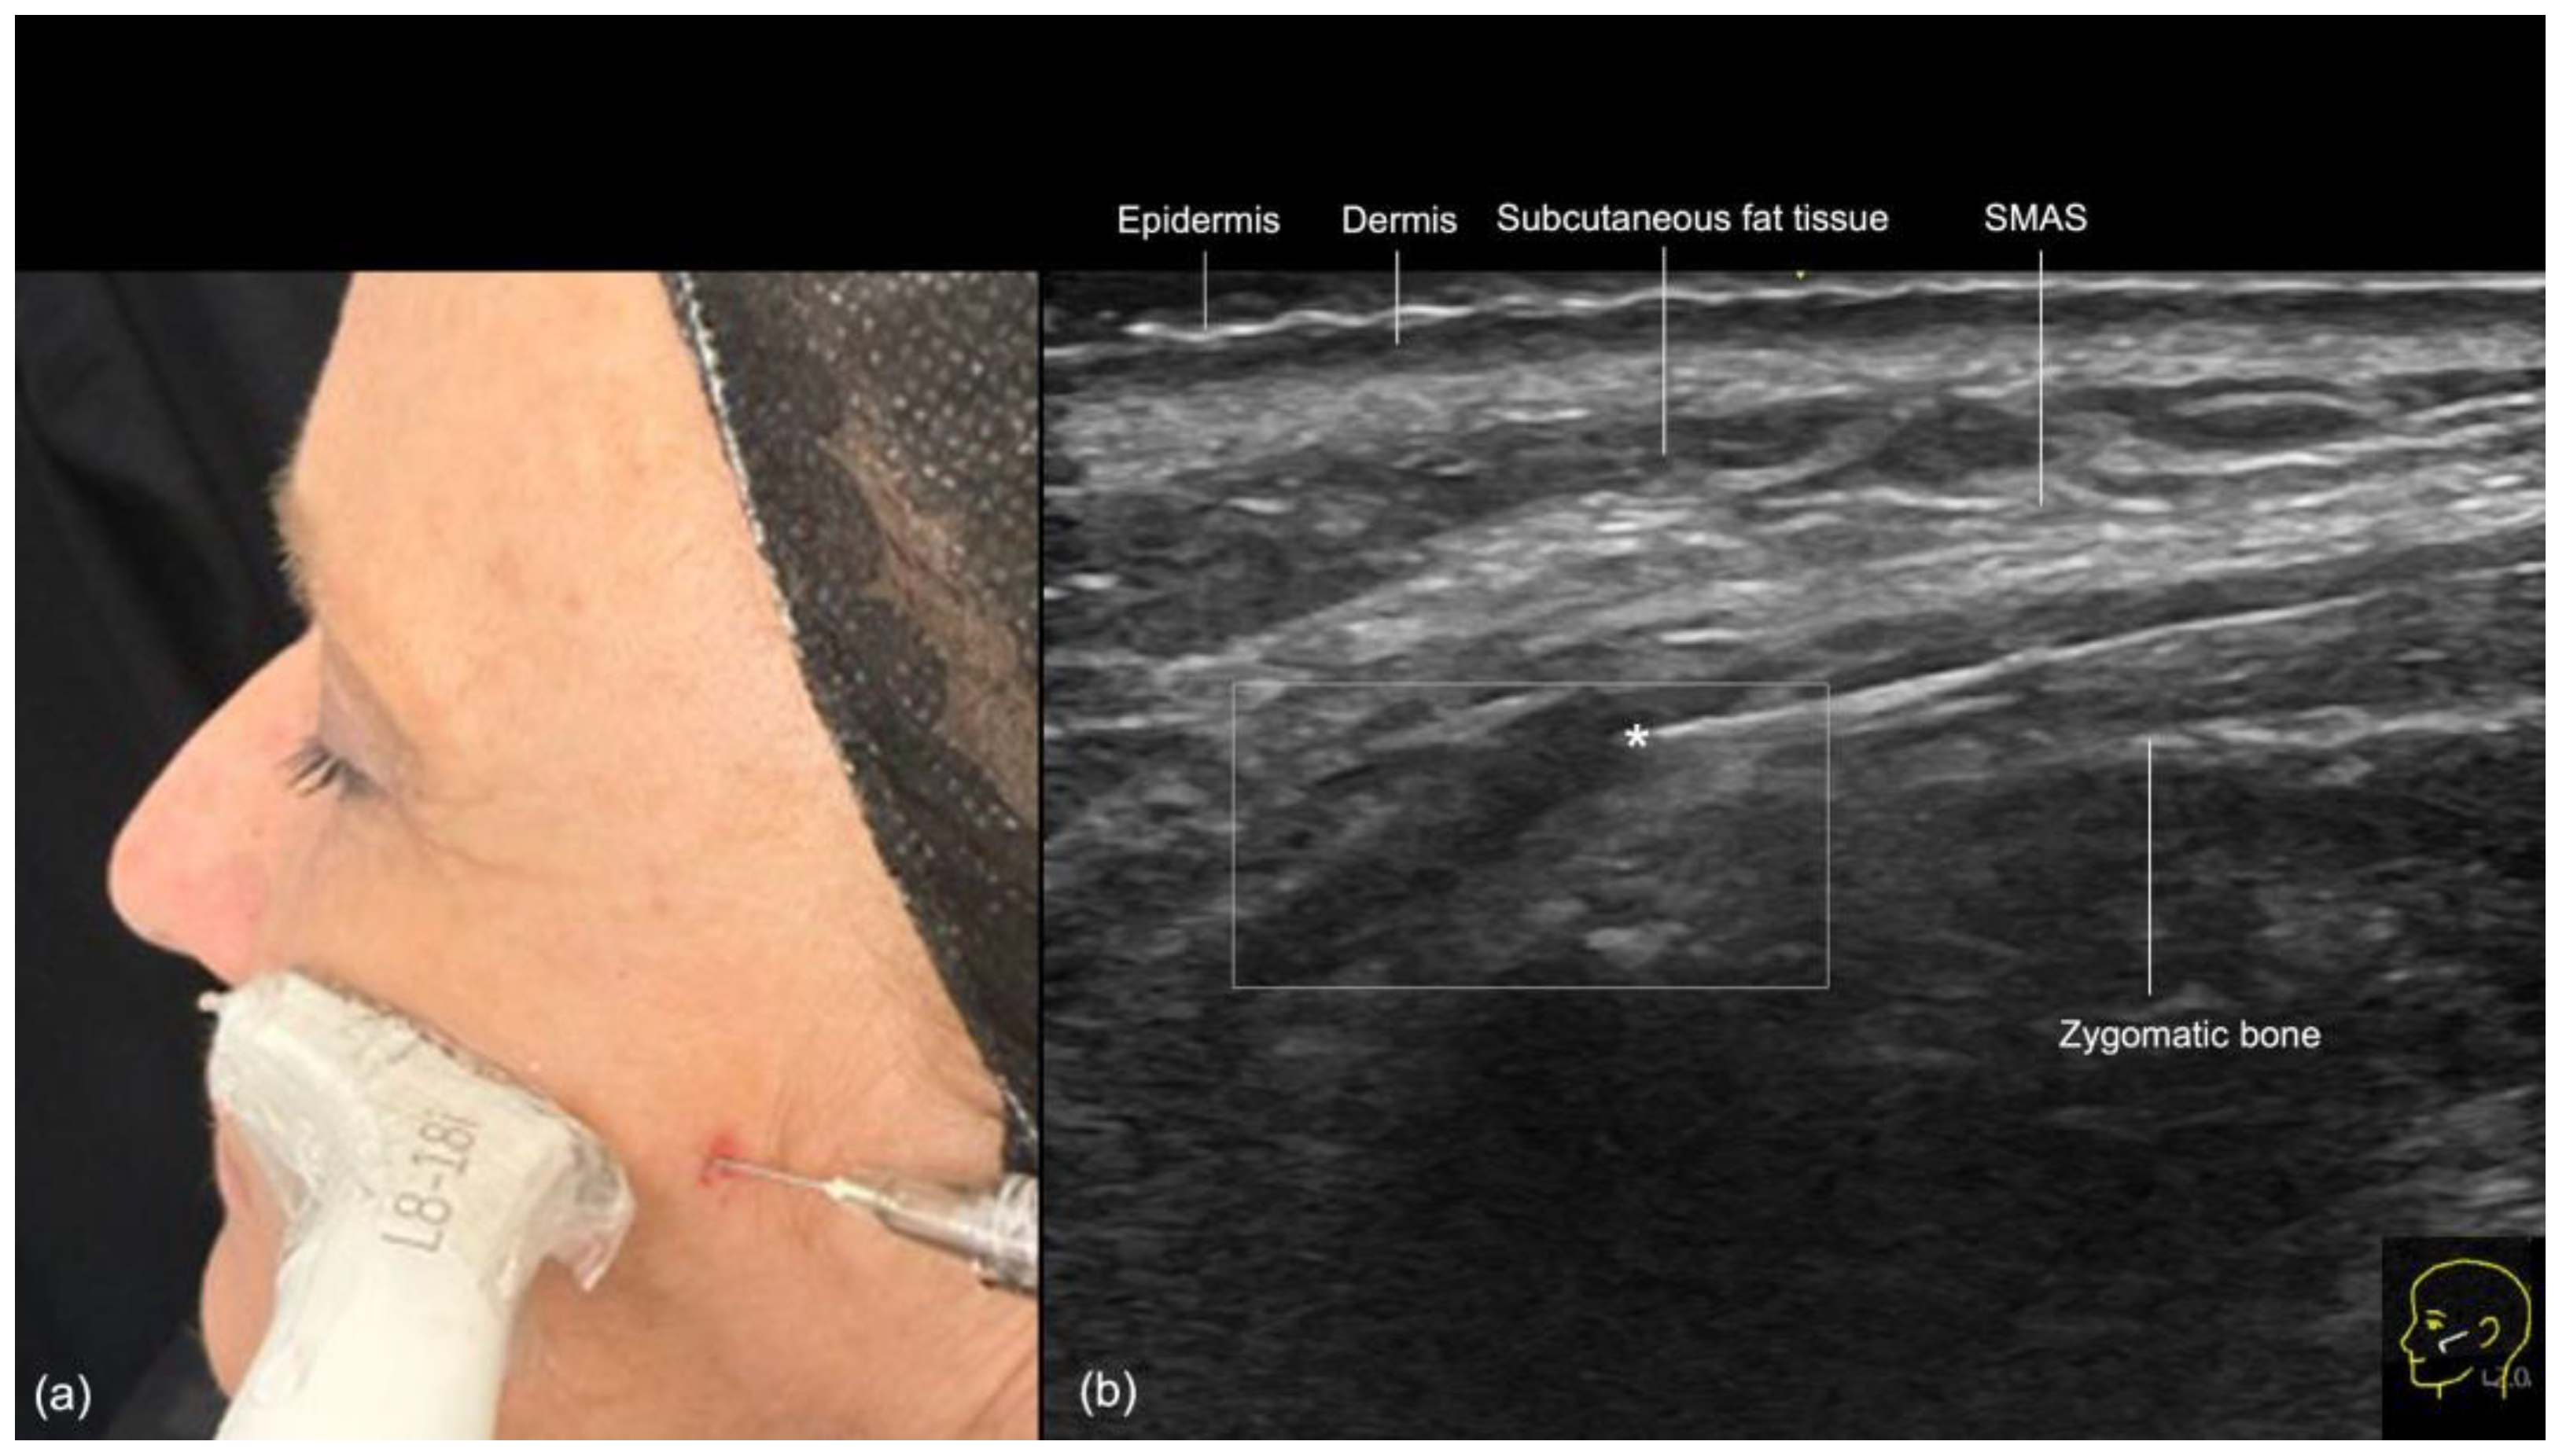

- Zygomatic Region

- Technique 1: Supraperiosteal filler placement

- Technique 2: Subcutaneous filler injection